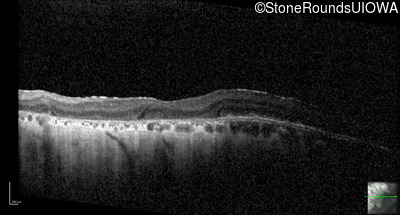

Optical Coherence Tomography - Right - 20/25 -2

Exemplar / OCT Stack